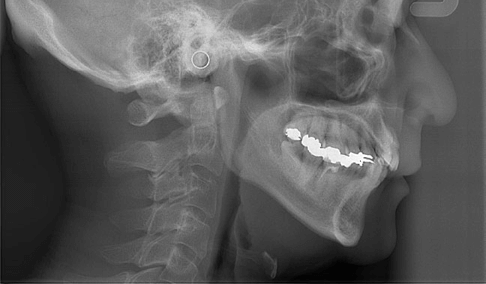

セファロ

矯正治療に欠かせない

頭部のレントゲンを撮影しますセファログラムとは歯や顎だけでなく、頭部も含めて撮影できる矯正歯科治療専用のレントゲンのことです。セファロを使って顎の形やバランス、歯の傾斜などを撮影することで、歯・顎・顔の全体的な変化を見ながら、治療の経過を把握することができます。